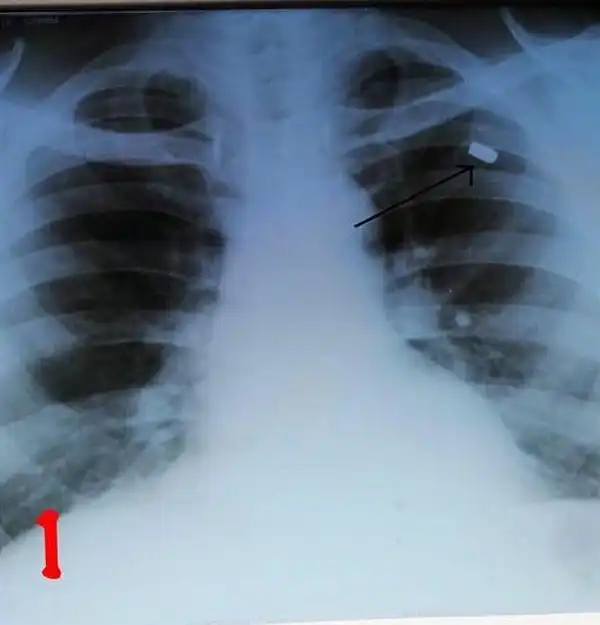

Врачи в Кабардино-Балкарии провели успешную операцию по извлечению пули из груди мужчины, который прожил с ней более 30 лет. По словам медиков, мужчина 1954 года рождения поступил в отделение с жалобами на ноющую боль в области груди, которая началась около месяца назад. Сделав рентгеновские снимки, медики обнаружили инородный предмет в грудной полости.

Как стало известно во время операции, инородным телом оказалась пуля. По словам медиков, она находилась в теле пациента уже более 30 лет, но начала создавать дискомфорт лишь некоторое время назад, когда сдвинулась с места.